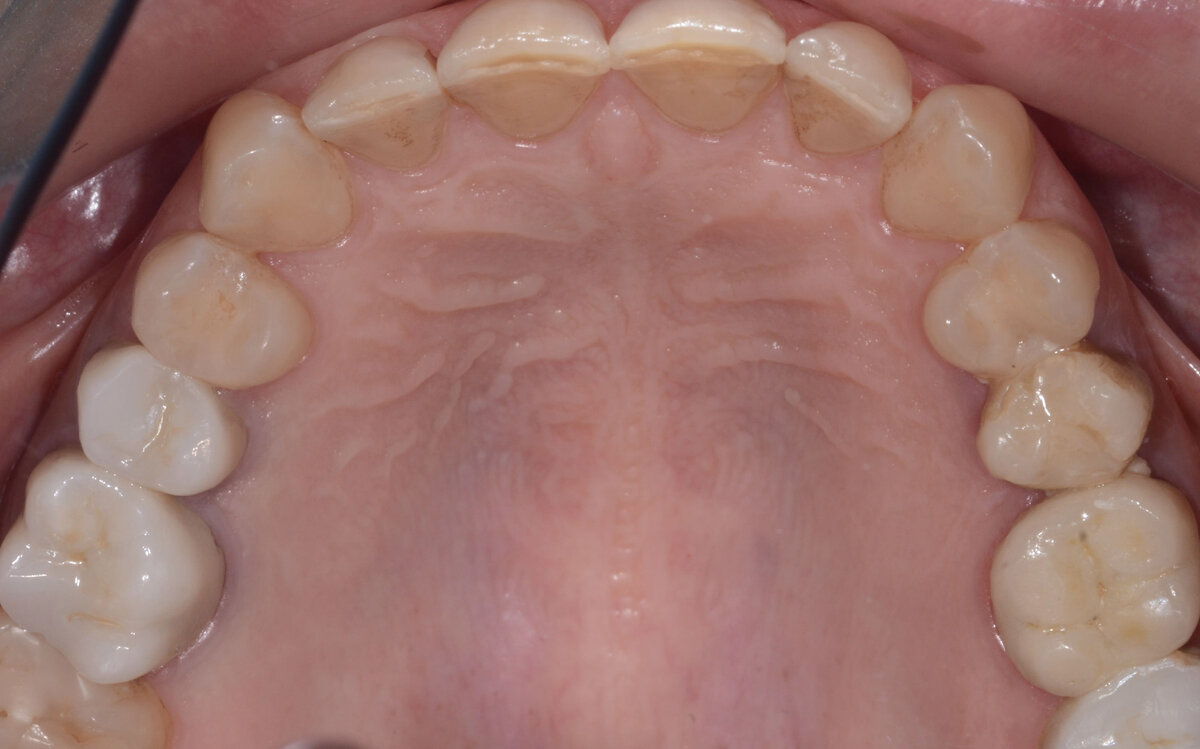

Пациентка обратилась в клинику с жалобой на отсутствие зубов и эстетические проблемы. Ей не нравилась ее улыбка, но в целом состояние зубов было неплохое. На верхней челюсти были сохранены все зубы, не было больших пломб и реставраций.

Мы провели обследование пациентки, сделали необходимые снимки, фотографии, КТ. Передние зубы по медицинским показаниям были в неплохом состоянии. Единственное, что беспокоило, это эстетика. Вместе с ней мы стали вместе изучать фотографии, чтобы принять единственное верное решение. Даже в этой ситуации можно сделать как отбеливание , так и виниры. Все зависит от того, насколько пациент хочет улучшить свою улыбку.

В любом случае, мы четко видим, что здесь ярко выражена стираемость зубов. На передних зубах режущий край с микросколами и неровными краями, что говорит о стираемости, плюс есть пигментация на контактах. То есть отбеливание - это конечно более щадящая процедура, но возник вопрос: удовлетворим ли мы эстетические пожелания пациентки о ее новой и красивой улыбке?

Вторая опция - это виниры. Здесь, конечно, четко прослеживаются показания к ним. А именно: пигментирование контактов и стирание зубов. Требуется необходимость изменения формы и длины зубов.